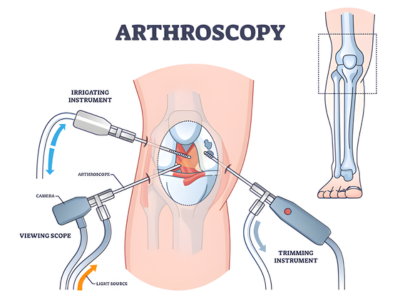

Minimally Invasive Techniques

Procedures designed to reduce pain, shorten hospital stay, and support faster recovery.

3. What is arthroscopy?

It is a minimally invasive procedure that uses small incisions and a camera to treat joint issues with a faster recovery.